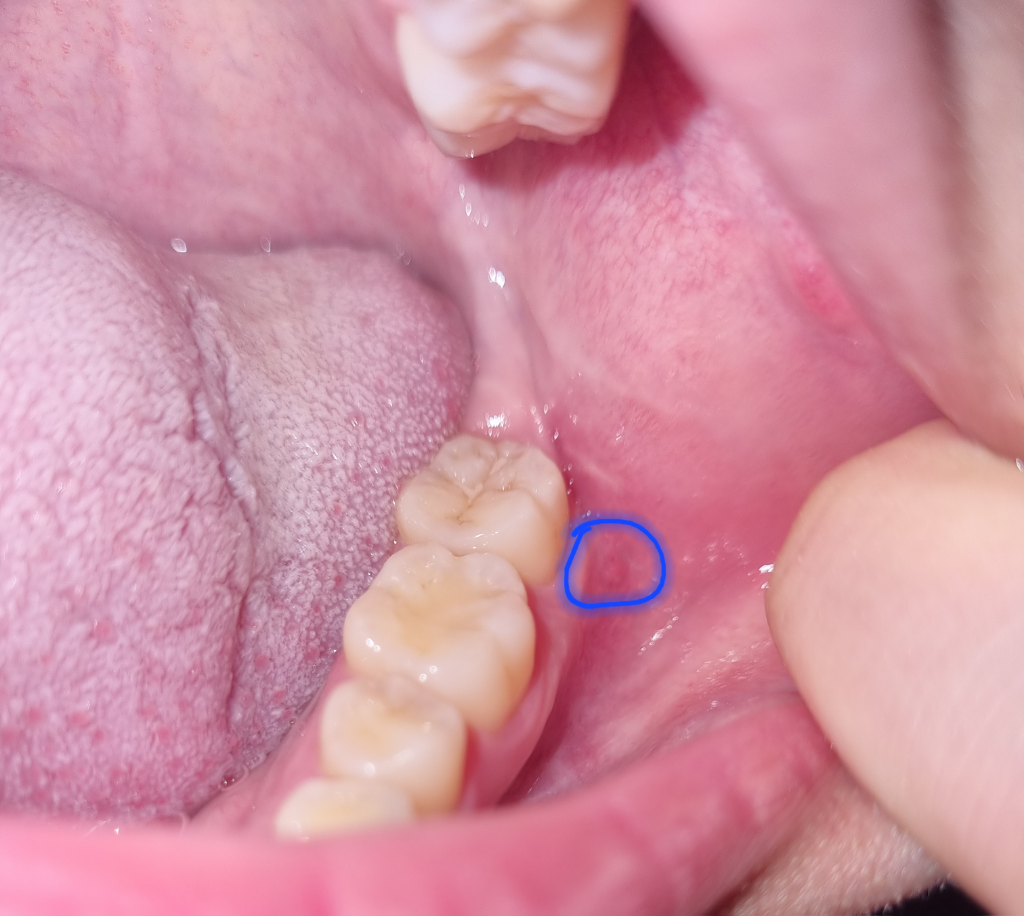

이거 구내염인건가요? 빠른 답변 부탁드립니다 사진첨부

잇몸이랑 입안 볼 사이 경계부분에 작게 뭐가 났어요 아프지는 않고 튀어나온거 같지도 않아요

다만 제가 저부분 양치를 너무 강하게 해서 주변부가 좀 빨개진 것 같긴 해요

통증이나 다른 증상 없는데 이런것도 구내염인가요? 아니면 자극에 의한 일시적 증상인가요?

구내염은 아니신거 같고 잇몸부위가 자극을 받아서 그런거 같습니다. 시간이 지나면 괜찮아 지실꺼에요.

현재 사진상으로 자극에 의한 일시적인 잇몸에 붉은 증상으로 보입니다. 우선은 해당부위에 강한자극은 피하고, 상태를 지켜보길 권합니다.

사진상으로 봤을때 구내염이 맞습니다 별 증상이 없을 수도 있고 수일내로 해당 흔적은 사라지게 됩니다

평소보다 피로하거나 스트레스를 받으면 생기기도 합니다